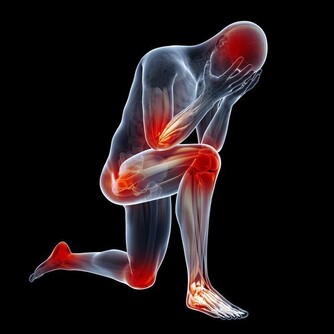

胯骨疼痛是許多人會遇到的疼痛症狀,它可能來自於骶髂關節、腰椎等多個部位的病變。當感到胯部或髂骨處隱隱作痛時,我們該如何判斷其成因?原因明確了,治療才能更有針對性。

胯骨疼痛是較常見的症狀,臨床上將其定義為髖關節周圍軟組織出現的疼痛感。胯骨區域包含肌肉、韌帶、神經、血管等多個解剖結構,任何一個部位發生病變都可能導致疼痛。

胯骨疼痛的確切部位各有不同,可能位於髖關節的內側、外側、前側或後側。臨床研究顯示,內側和前側疼痛較多。